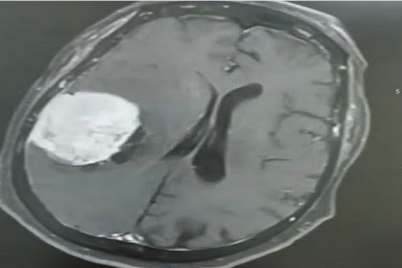

تمكّن فريق طبي متخصص بمستشفى ينبع العام عضو تجمع المدينة المنورة الصحي من إجراء عملية نوعية دقيقة لاستئصال ورم دماغي...